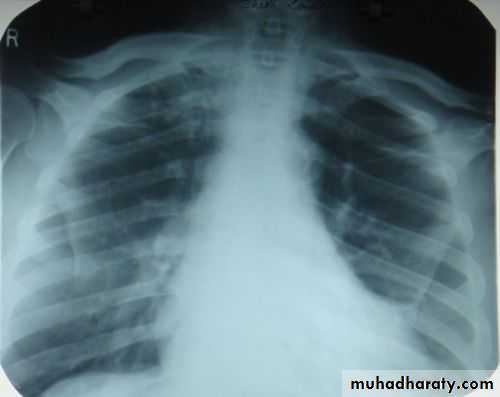

Pleural Effusion on Chest Radiographs.

Posteroanterior (A) and lateral (B) chest radiographs demonstrate the typical meniscoid appearance (arrows) in a patient with a left pleural effusion

Massive pleural effusion with mediastinal shift to the left.

(A) Chest radiograph

(B) CT coronal reconstruction. A massive effusion displaces the mediastinum to the left. CT shows the important pleural effusion together with the enhanced atelectatic left lung.

Note also the depression of the right hemidiaphragm (arrows).